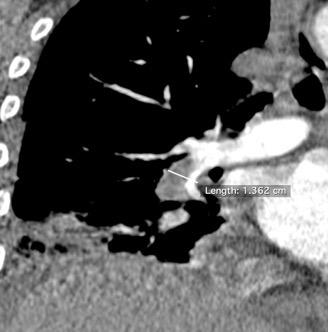

Tromboembolismo pulmonar.

Frecuencia del derrame:

Rx: 32%. TC: 47%

Unilateral. 85%

< 1/3 del hemitórax: 90%

Todos exudados

58% con eritrocitos

21% tabicación lo que causa demora en el diagnóstico

TEP. Empiema pleural. Atelectasia redonda

Porcel JM et al. Analysis of pleural effusions in acute pulmonary embolism: radiological and pleural fluid data from 230 patients. Respirology 2007/ Iguchi T et al. Desquamation of the subpleural lung parenchyma caused by empyema after pulmonary embolism: A case report. Respirol Case Rep. 2022 .